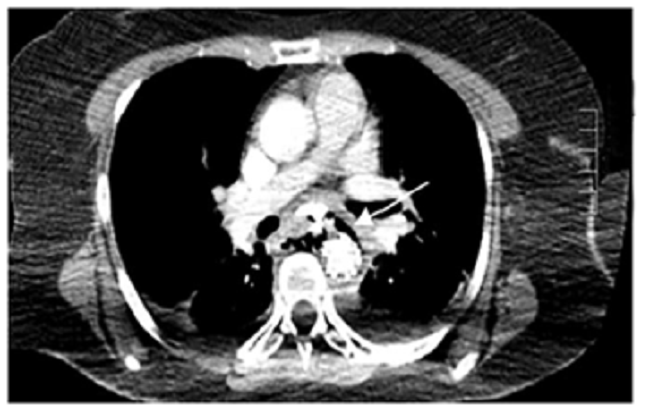

Se decidió practicar una nueva angiotomografía torácica con doble contraste, oral y endovenoso, en la que se observó la endoprótesis en la aorta descendente, extravasación del medio de contaste oral por la pared posterior del esófago, neumomediastino y derrame pleural bilateral, lo que confirmaba una perforación esofágica (figura 3).